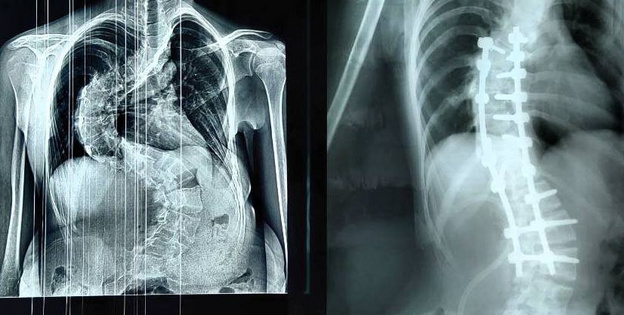

В кировском Центре травматологии выполнили операцию по коррекции тяжелой формы сколиоза у 14-летней пациентки. Позвоночник девочки был деформирован в S-образную форму, что угрожало нарушениями работы дыхательной и сердечной систем. Четырехчасовую операцию провела бригада врачей под руководством первого заместителя председателя правительства региона Дмитрия Курдюмова. Хирурги установили многоопорную винто-стержневую систему, выпрямив позвоночник и сохранив его функции. По словам специалистов, своевременное обращение позволило предотвратить необратимые последствия. Фото: минздрав Кировской области

В кировском Центре травматологии выполнили операцию по коррекции тяжелой формы сколиоза у 14-летней пациентки. Позвоночник девочки был деформирован в S-образную форму, что угрожало нарушениями работы дыхательной и сердечной систем.

Четырехчасовую операцию провела бригада врачей под руководством первого заместителя председателя правительства региона Дмитрия Курдюмова. Хирурги установили многоопорную винто-стержневую систему, выпрямив позвоночник и сохранив его функции. По словам специалистов, своевременное обращение позволило предотвратить необратимые последствия.

Фото: минздрав Кировской области